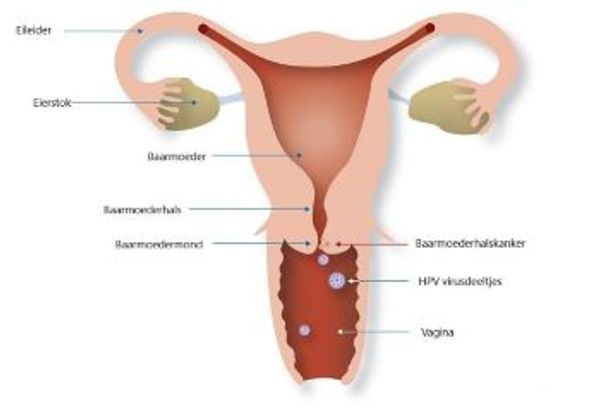

HPV – dat staat voor het Humaan Papilloma Virus – is een virus dat een aantal soorten kanker kan veroorzaken, waaronder baarmoederhalskanker. Acht op de tien mensen wordt tijdens zijn of haar leven, meerdere keren besmet met dit virus. Meestal wordt je er niet ziek van en merk je zelfs helemaal niets van de besmetting. Toch ben je, als je het virus hebt opgelopen, zelf wel besmettelijk en kun je dus zonder dat je dit weet anderen besmetten.

In principe wordt een HPV-virus overgedragen van mens op mens via seks. Niet alleen door het hebben van gemeenschap, maar ook door orale seks of door aanraking met handen of huid. Het kan via deze wegen de baarmoederhals, maar ook de geslachtsorganen en/of de mond- en keelholte besmetten. En deze besmetting kan zich dus uiteindelijk ontwikkelen tot kanker. Dit zijn; baarmoederhalskanker, kanker bij de vagina, de schaamlippen, anus, de penis en kanker in de mond- en keelholte.